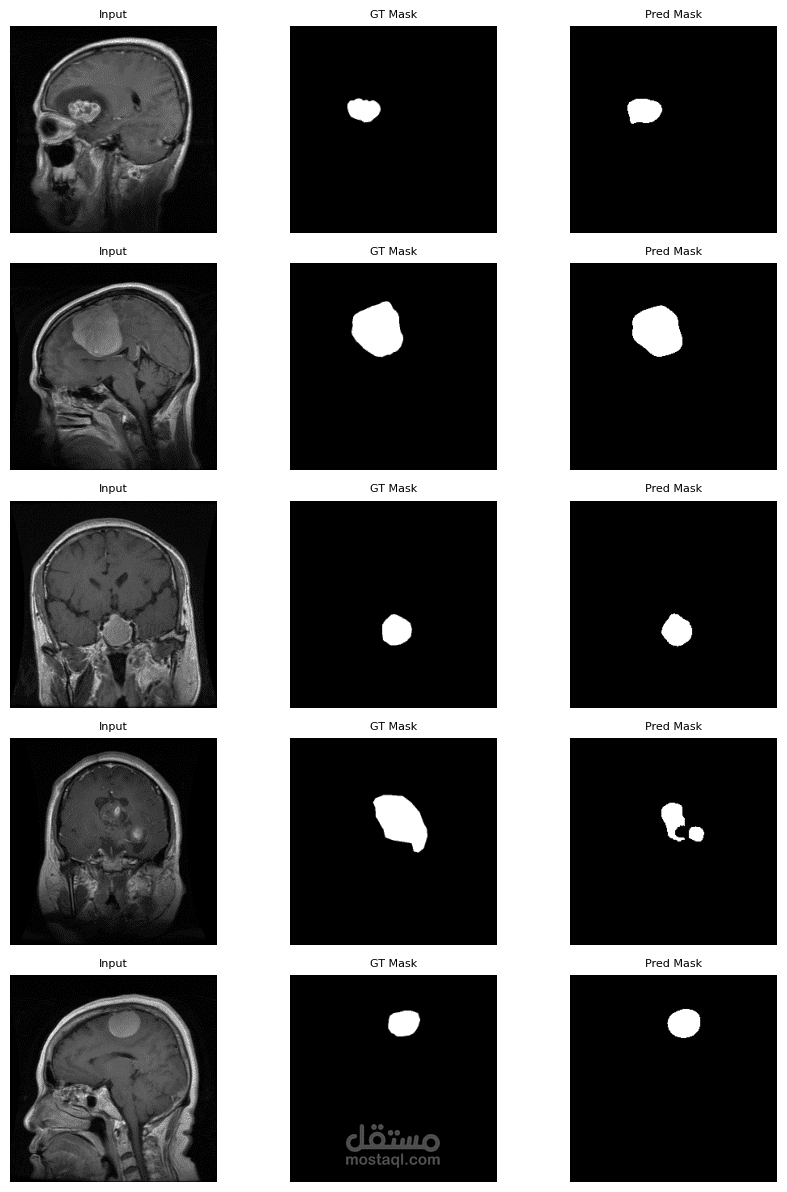

Computer Vision: Image Classification, Object Detection, Segmentation